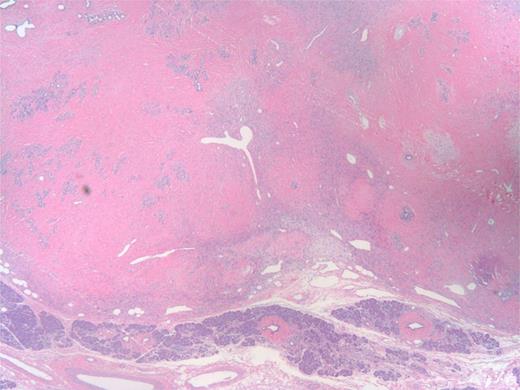

The specimen was a 3.5 ×3 ×3-cm white, firm, well-circumscribed mass located in the head of the pancreas (Fig. 3). The mass was found to be compressing the distal aspect of the main pancreatic duct. All 15 lymph nodes received in the specimen were negative. Histologically, the tumor is well circumscribed from normal pancreatic tissue and composed of spindle cells that in some areas form short ill-defined fascicles and in other areas are randomly arranged in a dense fibrohyaline stroma. A well-developed vascular network was visualized throughout the tumor with vessels of a stag horn appearance with thin hyaline wall and tumor growth around (Figs 4 and 5). No significant mitotic activity or tumor necrosis was noted. Immunostaining was positive for CD34 (Fig. 6) and BLC-2; focally for B-catenin, and focally weak staining for CD99, compatible with fibroblastic origin. The tumor cells were negative for the following cell markers: CD117, CAM5.2, AE1/AE3, EMA, synaptophysin, chromogranin, CD56, PR, SMA, Desmin, S100, MelanA and HMB45. The M1B1 proliferation index was low (<5%). These findings in combination are consistent with a SFT.

Low power of tumor (upper part) and uninvolved pancreas (bottom). The tumor has stag horn vessels, cellular areas of spindle cell proliferation and hyalinized ‘keloid areas’.